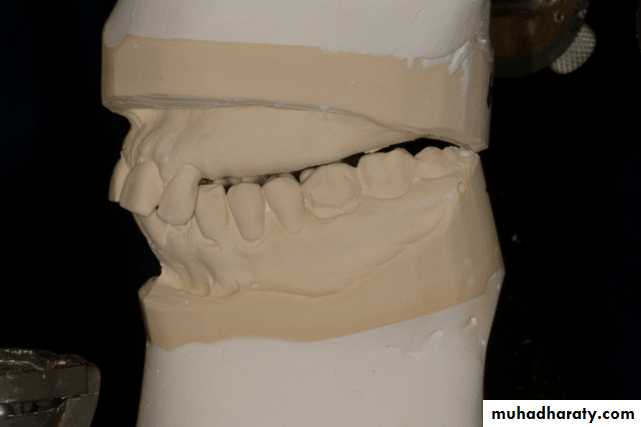

Diagnostic impressions and casts

A diagnostic procedure is incomplete unless it includes the evaluation of accurate diagnostic casts.Permits analysis of contour of both hard and soft tissues of the mouth

Determines the type of restorations to be placed on the abutment teeth

Determines the need for the correction of exostoses, frena, tuberosities, and undercuts

The casts are surveyed, the proposed design is drawn on the casts.4/2/2018

Diagnostic casts are valuable for research purposes and forensic information as they provide observable, precise geometry of the teeth and jaws

Occlusion constantly changes, and comparison of the changes on stone casts provide valuable information to the practitioner and can be used to educate the patient.

The designed casts serve as a blue print for the placement of restorations, the re contouring of teeth, and preparation of rest seats.

Aid in the presentation of proposed treatment plan to the patient.

The mounted diagnostic casts permit analysis of the patients occlusion, adequacy of inter arch space, and of the presence of over erupted or malposed teeth and tuberosity interferences.4/2/2018